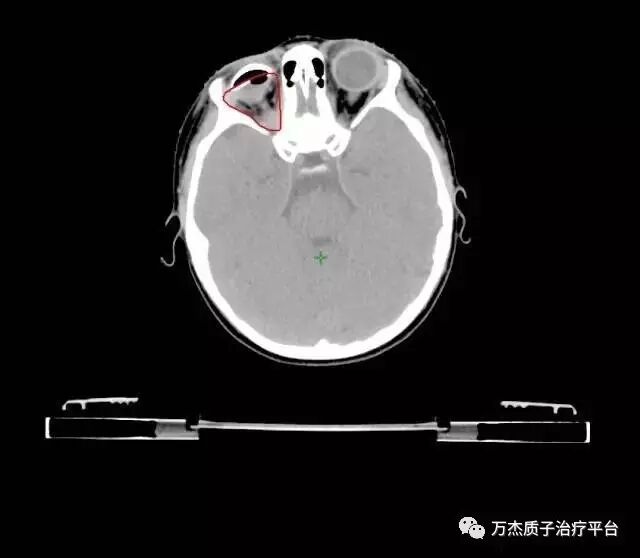

病情:右侧视神经上皮细胞瘤10月余。于2008年3月眼科检查发现右侧视神经萎缩,2008年4月14日查头颅MRI示:右侧眼球后占位。于2008年8月19日手术活检病理为:视神经上皮细胞瘤。2008年12月2日----2009年3月16日行3个周期化疗(HIT-SKK.2000)第一周期化疗后复查CT病灶有轻微改善,第二周期后复查肿瘤进展。于2009年3月26日行外科手术眼球摘除术,肿瘤切除病理视神经上皮细胞瘤,术后置一假体。术后于2009年4月20日—2009年9月11日行4周期化疗(HIT-2000)于2009年7月14日复查:残留灶缩小。2009年11月17日PET示:病灶区FDG摄取活跃,考虑残留区病灶进展。为行质子治疗来我院。入院时间2010年2月9日。入院后行质子治疗剂量DT60CGE/30F/35d

治疗前图像:

质子治疗剂量分布:对侧眼睛、视神经及脑组织均受到良好保护;

俄罗斯3岁小患者五年随访复查,未见复发迹象。